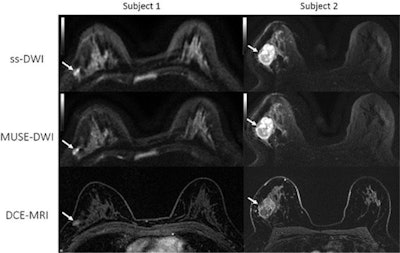

"MUSE DWI yielded significantly improved image quality compared with single-shot DWI in phantoms and participants," wrote the international team of authors, led by Dr. Isaac Daimiel Naranjo from the breast imaging service at Memorial Sloan Kettering Cancer Center in New York City.

"In accordance with these previous investigations, our preliminary study in the breast found that the quality of the image with MUSE DWI was ostensibly better, resulting in improved lesion delineation compared with single-shot DWI," the authors wrote.

Further, MUSE DWI demonstrated significantly better signal-to-noise ratio and improved fat suppression and artifact correction. The researchers also found no difference in the apparent diffusion coefficient values of the two procedures.